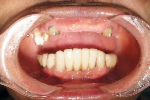

上顎全額的インプラント症例

上の全ての歯がぐらぐらな状態で左上の歯(写真向かって右上)が痛いとご来院。入れ歯は絶対に嫌ということで、まずは痛む左上(レントゲンでは右上)を抜歯、サイナスリフト(骨の移植)を併用しインプラント埋入して残りの歯で無理やり仮歯を支える。左上インプラントが生着し左で咬めるようになったら前歯(鼻の下がくぼんで老人様顔貌を避けるため骨の厚みを出す手術併用)、右上の歯はすべて抜歯して(ソケットリフト併用)しインプラント埋入。生着に時間のかかる日本承認の従来型のインプラントだったので計1年以上の治療期間を要しましたが一度もご自身の歯で咬めない時期はないようにしました。